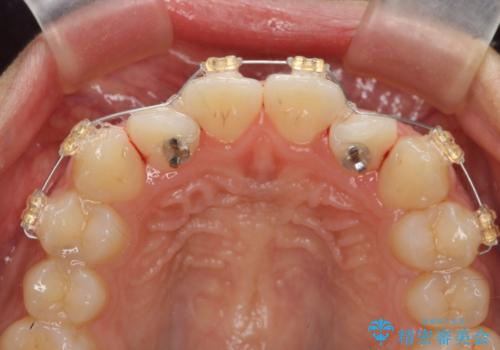

- インビザライン +部分ワイヤー矯正

上顎前歯のみの部分ワイヤー治療を約6ヶ月行い、ねじれの問題を解決したのち、マウスピース矯正で細かな歯列を整えていきます。